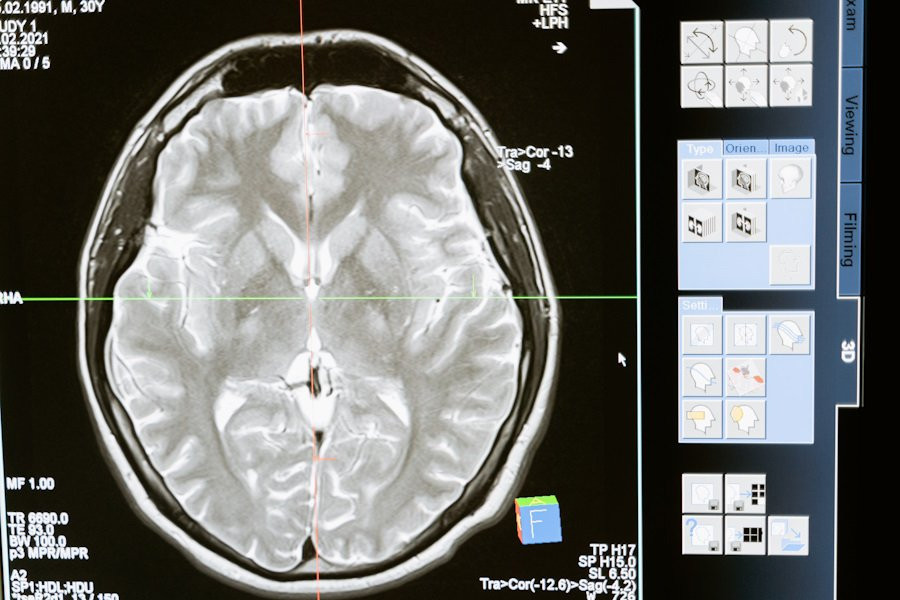

Исследования, опубликованные на портале eLife, предлагают новую перспективу на лечение деменции и психических расстройств, таких как шизофрения, аутизм и болезнь Альцгеймера. Ученые выявили изменения в кислотности мозга, что может стать ключом к разработке эффективных методов борьбы с этими состояниями.

Исследование показало, что повышенный уровень лактата, конечного продукта гликолиза, может служить потенциальным индикатором метаболических изменений в мозге во время его возбуждения. Эти изменения, в свою очередь, могут привести к снижению уровня pH мозга, что наблюдается у пациентов с различными нервно-психическими расстройствами.

Результаты показали, что снижение pH мозга и повышение уровня лактата характерны для нескольких моделей депрессии, эпилепсии, болезни Альцгеймера и некоторых форм шизофрении. Также было обнаружено, что плохая работа рабочей памяти связана с повышенным уровнем лактата в мозгу.

Эти результаты указывают на то, что изменения в pH мозга и уровне лактата могут быть общими чертами различных нервно-психических расстройств, независимо от их конкретной природы. Это открытие открывает новые возможности для разработки трансдиагностических методов лечения, направленных на коррекцию баланса возбуждения и торможения в мозге, что в свою очередь может улучшить когнитивные функции пациентов.